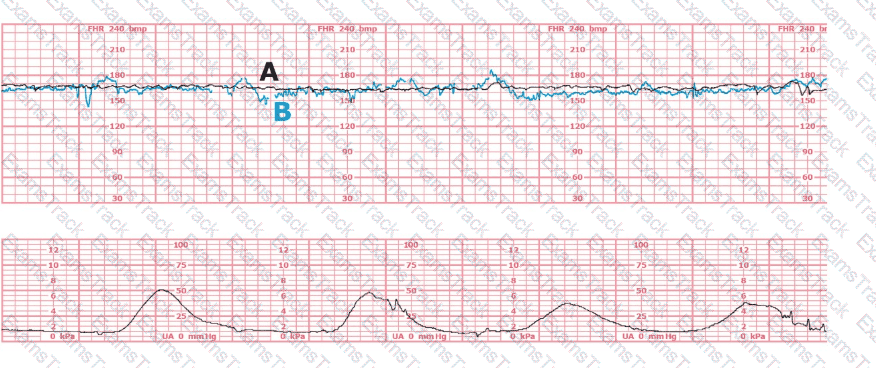

A patient presents at 38-weeks gestation with complaints of decreased fetal movement and ruptured membranes. The fetal heart rate is not able to be determined with an external ultrasound monitor. A spiral electrode is placed, and the tracing shows a rate of 90 bpm. What is the next most appropriate action?

The black pattern represents the heart rate pattern for Baby A. The blue pattern represents the heart rate pattern for Baby B. A possible etiology of the baseline fetal heart rate of Baby A is: